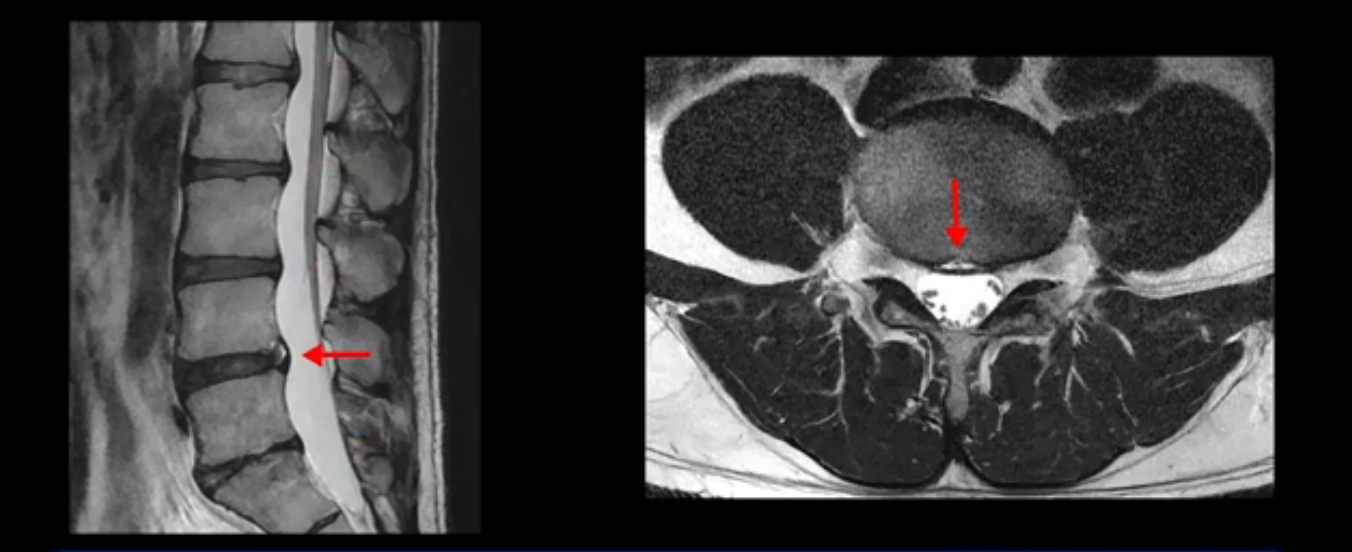

4번 5번은 가운데로 섬유륜이 찢어져서 디스크가 살짝 밀려나와 있지만 역시나 최근에 찢어지고 밀려나온 걸로 판단되지 않고 오래 전에 찢어진 흔적으로 보입니다.

왜 최근에 찢어진 급성이 아니고 오래된 거라고 하는지 이 부분도 뒤에 한꺼번에 설명 드리겠습니다.

앞서 1번 2번, 4번 5번, 5번 1번의 디스크가 찢어지고 조금 밀려 나온 게 최근에 찢어진 게 아니고 오래된 걸로 보인다고 말씀 드렸죠. 왜 그럴까요? 만약 급성으로 찢어진 것이라면 아주 심한 디스크성 통증이 있겠죠. 기침이나 재채기를 하면 심하게 아프고 허리를 조금만 구부리거나 비틀면 아주 날카로운 통증들이 생길 겁니다. 그런데 이분은 이런 증상이 전혀 아닙니다. 또 디스크의 밀려나온 정도도 전혀 심하지 않기 때문에 이분이 가지고 계신 양쪽 다리 저림, 특히 이분은 누워있을 때도 양쪽 발이 발가락까지 쑤신다고 하는데 이정도 디스크 때문에 그런 증상은 생길 수가 없는 겁니다. 이처럼 이분의 가벼운 디스크 탈출은 이미 오래 전에 진행되었고 섬유륜 자체는 이미 아문 상태인데도 디스크내장증을 진단받은 환자들 중에는 본인이 섬유륜 파열 환자라고 끝까지 믿는 분들이 많습니다. 다시 말하지만 디스크내장증이라는 진단을 받은 환자들을 보면 거의 전부 다 섬유륜 파열 증상이 아닙니다. 증상이 완전히 다릅니다. 진단이 애초에 잘못되면 어떤 치료를 받아도 좋아질 수 없습니다.

이분은 어떤 한 병원에서 디스크 내장증 얘기를 들으셨는데요. 여기 보시는 것처럼 4번 5번의 하얀 HIZ(High Intensity Zone)을 보고 디스크 내장증의 근거로 얘기하는 병원들이 있는데,

이 HIZ는 섬유륜이 찢어졌다가 이미 아문 뒤에도 얼마든지 보일 수 있는 흔적일 가능성이 있어서 재채기를 하면 아픈지, 허리를 구부릴 때 날카로운 통증이 생기는가 등의 증상으로 구별해야 하는데 MRI만 보고 HIZ가 보이면 그게 마치 통증의 원인인 것처럼 얘기하는 의사들이 있습니다. 이분 MRI를 자세히 보고 증상을 정말 자세히 들어본 의사가 있었더라면 다른 환자분들처럼 증상과 MRI가 일치하지 않는다는 얘기를 들을 수 있었을 텐데 이분은 그런 얘기는 듣지 못했습니다.